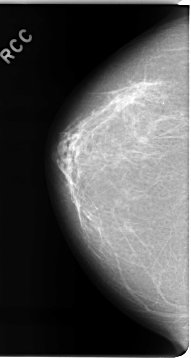

C_0075_1.RIGHT_CC

RIGHT_CC LINES 4648 PIXELS_PER_LINE 2472 BITS_PER_PIXEL 12 RESOLUTION 50 NON_OVERLAY